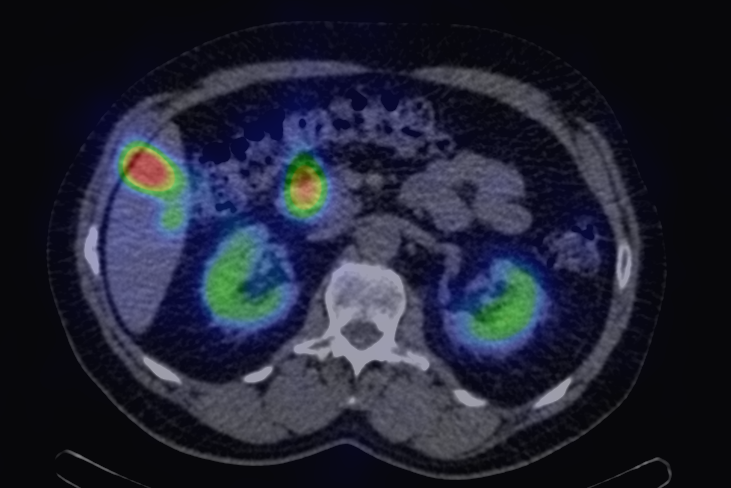

The most common clinical use of FDG-PET is in the form of whole-body scan, with oncologic indications. The majority of malignant tumors operate with higher energy consumption and show an increased glucose metabolism, consequently an increased uptake of FDG. The grade of malignancy is usually proportional to the rate of uptake. This method is useful in oncologic diagnostics, since it is capable to differentiate benign lesions from malignant ones. Whole-body PET imaging is capable to detect the primary tumor with local nodal metastases as well as distant metastatic lesions (staging) in one examination. (Figure 10.)

In the staging of malignant diseases FDG-PET is extremely important, since it has a greater sensitivity and specificity than the morphologic imaging modalities.

This is most certainly true in case of imaging metastatic lymph nodes. Morphological imaging methods utilize size as the only reliable criteria for the differentiation of a metastatic lymph node. FDG-PET detects metabolic changes in the metastatic lesions independently of their actual size. This way, normal sized metastatic lymph nodes can be identified, as well. Larger lymph nodes that are non-metastatic in nature, but for other reasons show abnormal enlargement can also be differentiated. (Figure 11.)

11. FDG PET-CT. Transversal plane fused (a) and CT (b) image. Small (normal sized) metastatic lymph node on the right side retrocrurally showing increased radiopharmaceutical uptake.